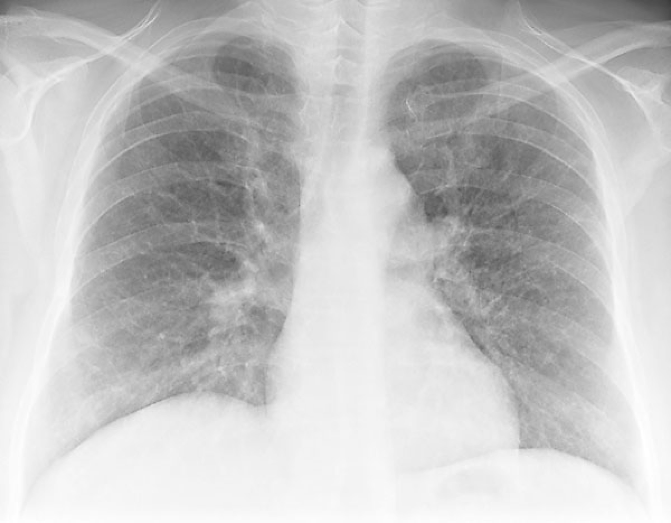

Radiographic Evaluation

- Bacterial

- Unilateral, lobar, air bronchograms

- Viral

- Diffuse or perihilar, bilateral